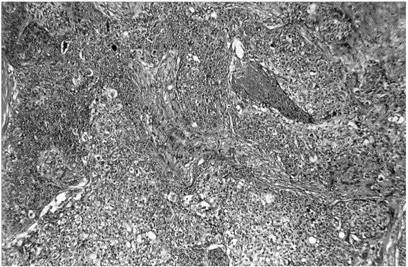

Fig. 7.9 - Epiteliom spinocelular (aspect histopatologic)

q carcinomul spinocelular include 10-15% dintre tumorile maligne ale pleoapelor si afecteaza mai frecvent pleoapa superioara si unghiul extern.

Clinic are un aspect vegetant, ulcerativ sau infiltrativ. Din punct de vedere evolutiv este mult mai agresiv decat carcinomul bazocelular, datorita caracterului invadant si metastazelor pe care le determina. Diagnosticul se pune pe examenul anatomopatologic (Fig. 7.9).